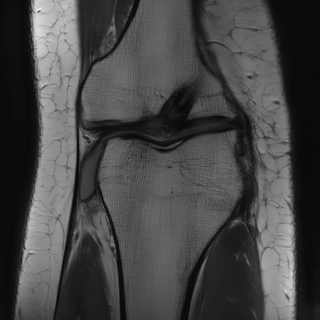

While the modeling of is mostly a question of obtaining appropriate forward and noise models (which is an important research direction on its own), the prior distribution, respectively regularizer, has been subject to a lot of research in particular in inverse imaging problems, with popular examples being Tikhonov regularization [68, Section 5], total variation regularization [158] and its generalization to higher-order approaches [33, 32]. As a consequence of the high complexity of image data, hand crafted methods for solving inverse problems seemed to reach a limit in terms of empirical performance. However, in the past decades, data driven approaches were able to significantly push forward the boundaries of reconstruction quality with appropriate priors. An illustrative example in this context is provided in Figure 1, were the performance of the hand crafted TV prior [158] is compared to the performance of the neural-network based approach of [83] for subsampled MRI.